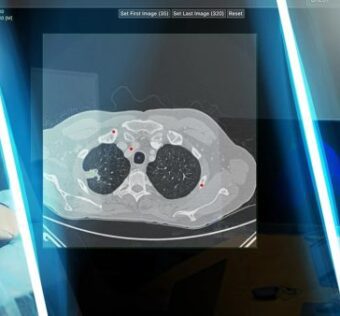

![]() GigXR and DICOM Director Introduce Three-Dimensional Medical Image Learning Using Holographic CT Scan and MRI Representations

DistilINFO Hospital IT - (Wednesday August 9, 2023) GigXR and DICOM Director have introduced the DICOM XR Library, utilizing hyper-realistic 3D medical images from MRI and CT scans. This collaboration enhances medical education, enabling holographic anatomy and pathophysiology learning. Learners can explore… ![]() Public open to virtual care, but lack of understanding could block progress